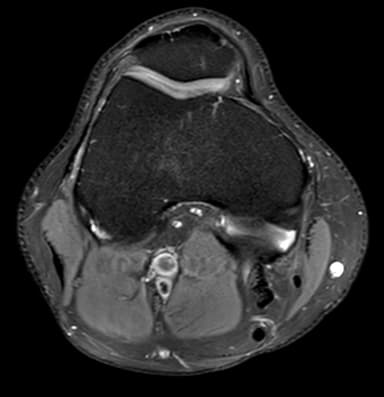

Eksempler fra reelle MSK-kontekster, herunder skulder, knæ, ankel og håndled, hvor strukturerede second opinions ofte giver størst klinisk værdi.

Komplekse skader, smerter, instabilitet, sene/ligament‑patologi, marvabnormiteter og postoperative tilfælde.